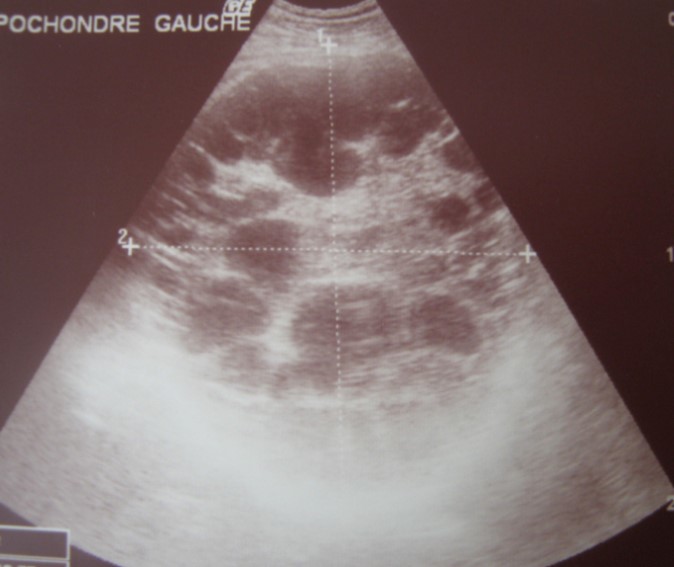

A 17-year-old young man admitted to our department with the complaint of abdominal pain localized in the left upper quadrant for the last 3 months. His physical examination revealed a splenomegaly. Immunoblot assay for Echinococcus was positive. His laboratory tests showed normal results of the serum and urine examinations, No eosinophilia was found. Chest X-ray revealed no pathological signs. An abdominal ultrasonography showed a 20 cm multivesicular cystic mass of spleen (figure 1). Contrast enhanced CT scans detected a huge single 20×16×18cm cystic mass located in the spleen. It had well-defined borders and contained multiple, round, daughter cysts in the periphery of the lesion with calcification (Figure 2, Figure 3, Figure 4). The patient underwent a laparotomy. A large splenic cystic mass was identified, attached to diaphragm, and tail of the pancreas (figure 5). The abdomen was packed with 10% hypertonic saline soaked pads in order to protect peritoneal soilage. A partial cystectomy without splenectomy was performed. Histologic examination of the specimen resection showed an echinococcal organism residing within the hydatid cyst . The patient was discharged after 4 postoperative days. 600 mg per a day of Albendazole therapy was instaured postoperatively and continued for 6 months. Two years after surgery the patient is well with disease free.

Figure 1.Ultrasonography showing a 20 cm multivesicular cystic mass of spleen

Ultrasonography showing a 20 cm multivesicular cystic mass of spleen